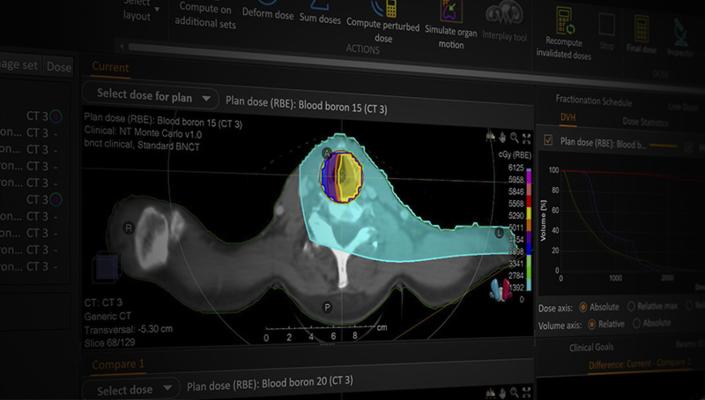

Since the launch, two important driving forces have been guiding stars in the development of RayStation; to offer the market's most advanced treatment planning system and for RayStation to support all available treatment machines. Today, no other treatment planning system supports such a wide range of treatment techniques and delivery systems as RayStation does.